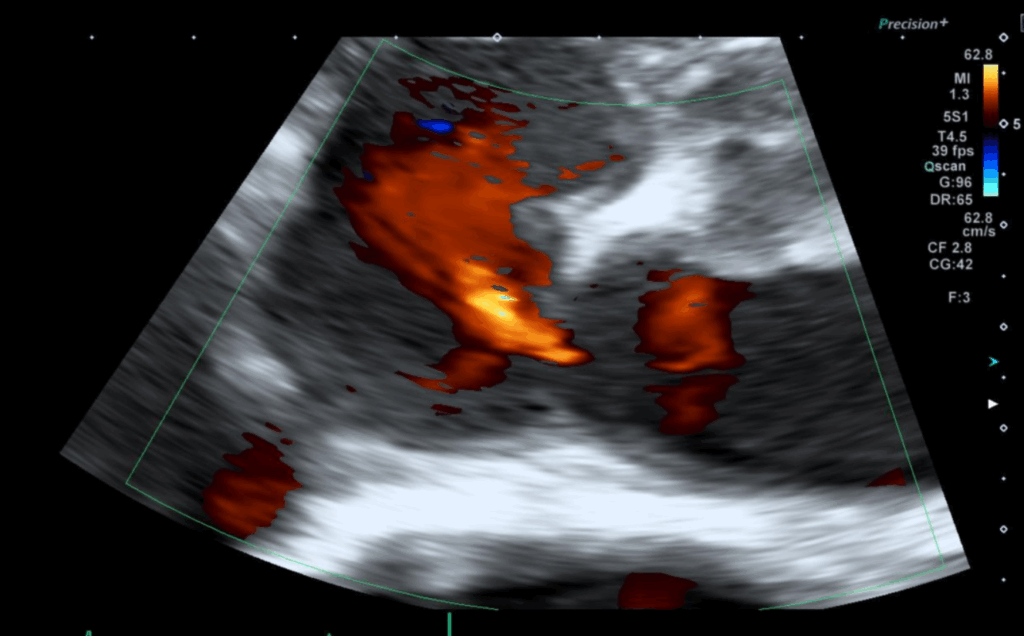

심초음파에서 좌심방과 우심방 사이에 막혀있어야 하는 중격 부분이 막히지 않아 붉은색 혈액 흐름이 관찰되었고 심방중격결손으로 판단했습니다. 환자분은 이전에 선천성 심장 이상소견에 대해 알지 못하는 상태이므로 대학병원으로 진료 연계를 진행하였습니다.

• 좌심방과 우심방 혈류 이동 관찰 좌심방과 우심방 혈류 이동 관찰